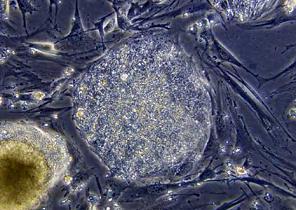

Her ikisinin de küçük oğullarının ciddi sağlık sorunları bulunan İşçi Partisi lideri ve Başbakan Gordon Brown ile Muhafazakar Parti lideri David Cameron ise kanser, parkinson ve alzheimer'a çare oluşturabilecek melez embriyolar üretilmesine olanak sağlayan yasayı desteklemesi için gruplarına çağrıda bulundu, kendileri de bu yönde oy kullandı. Yasanın kabulüyle bilim adamlarının insan-hayvan hücrelerinden oluşan embriyolar üretmesi, bunların 14 gün kadar korunup içlerinden kök hücrelerinin alınması, bu hücrelerin de hastalıkların tedavisinde kullanılması mümkün olabilecek. Yasa, "melez embriyoların" kadın ya da hayvan rahmine yerleştirilmesini ise yasaklıyor.